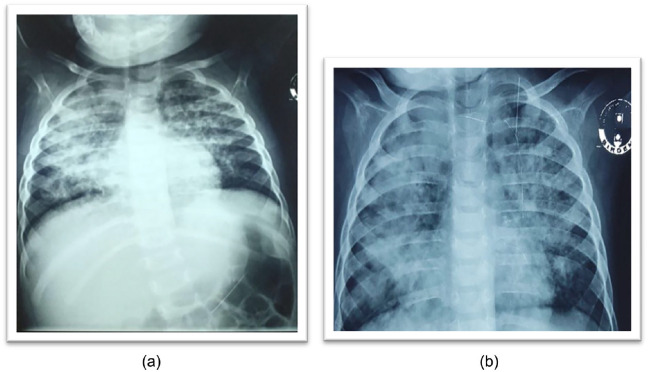

A 7-month-old girl had been suffering from progressively deteriorating pneumonia despite getting multiple courses of broad-spectrum antibiotics as well as anti-fungal drugs for adequate duration. To find out the cause behind this deterioration, the patient underwent thorough clinical and relevant laboratory evaluation including chest radiology & imaging, screening for primary immune deficiency disorders (PID), cystic fibrosis, tuberculosis, invasive fungal pneumonia, congenital heart disease, covid pneumonia, TORCH etc. but failed to solve the mystery. Upon further detailed re-evaluation, it was discovered that the child had a history of being forcefully fed lentil-based khichuri (a rice-lentil mixed dish) during her weaning process and diagnosis was finally confirmed as hypersensitive pneumonia due to lentil aspiration by a high level of IgG, specific to lentil antigen. Treatment was commenced with prednisolone resulting in significant improvement in her clinical and radiological condition within 72 hours.

Abstract Image